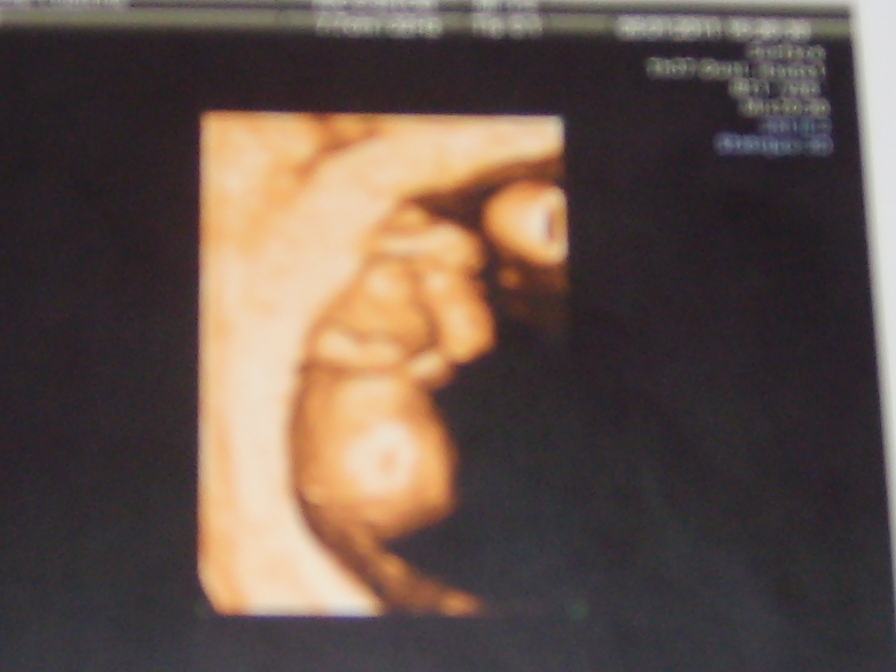

si tu veux je peux te faire voir une écho 3d de ma fille, on la voyait très bien et la crevette j'ai mis une écho sur le post la grande surprise si tu veux voir.